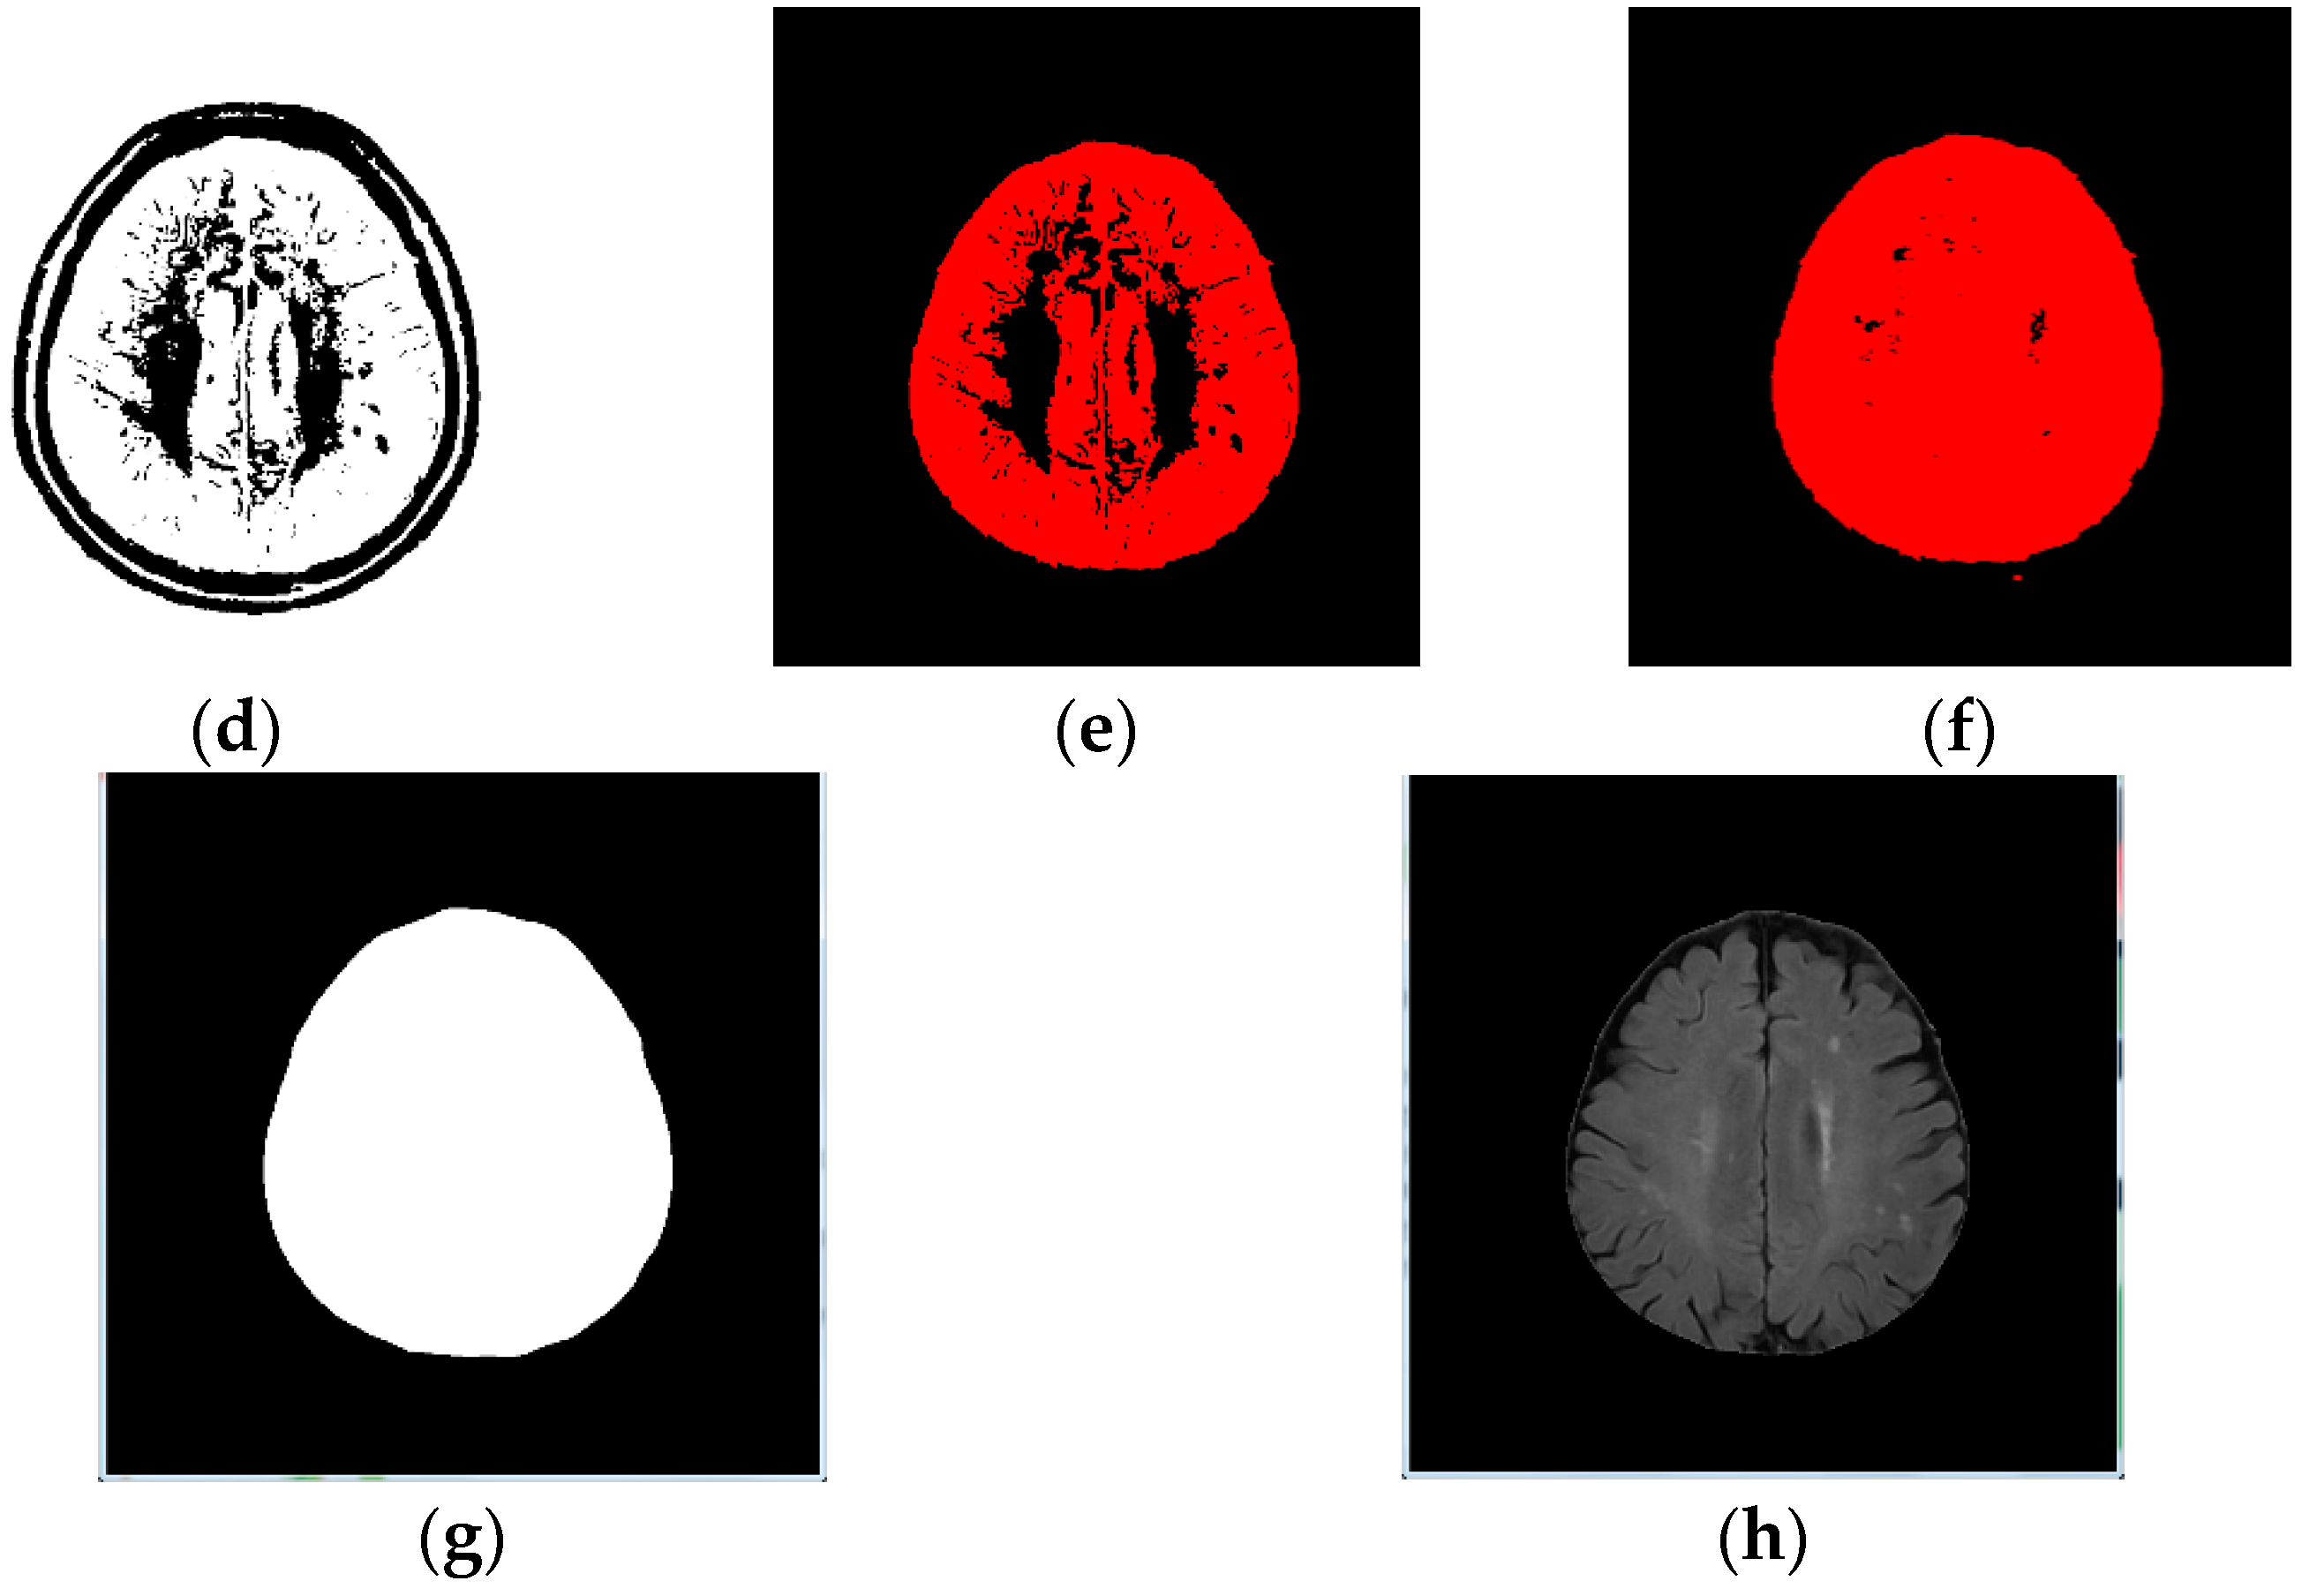

- Image binarization: We made sure the cranium (head shell) with the maximum region in image (Figure 1b);

- Image inverse binarization: The image from step 1 was adopted the inversed-binarization method in order to obtain the cerebrum region (Figure 1d,e);

- Identify the cerebrum region: The cerebrum region was obtained from step 3 and then compared with the region obtained by step 2. The union of the two step regions was calculated to identify the cerebrum region (Figure 1f);

- Perform median filtering to remove noise (Figure 1g); and

- Calculate the actual size and position of the brain (Figure 1h).